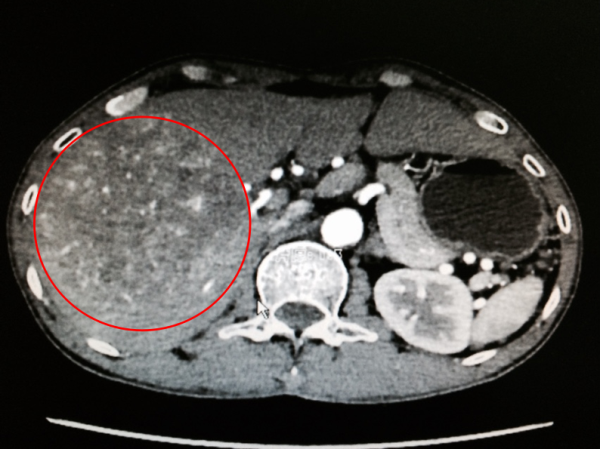

手术前CT图:红圈为肝肿瘤